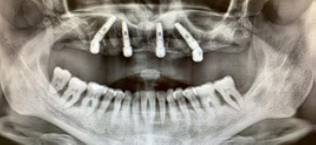

Classico esempio di riabilitazione su full arch secondo la tecnica di Malò